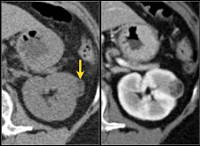

D30.0 Доброкачественное новообразование почки